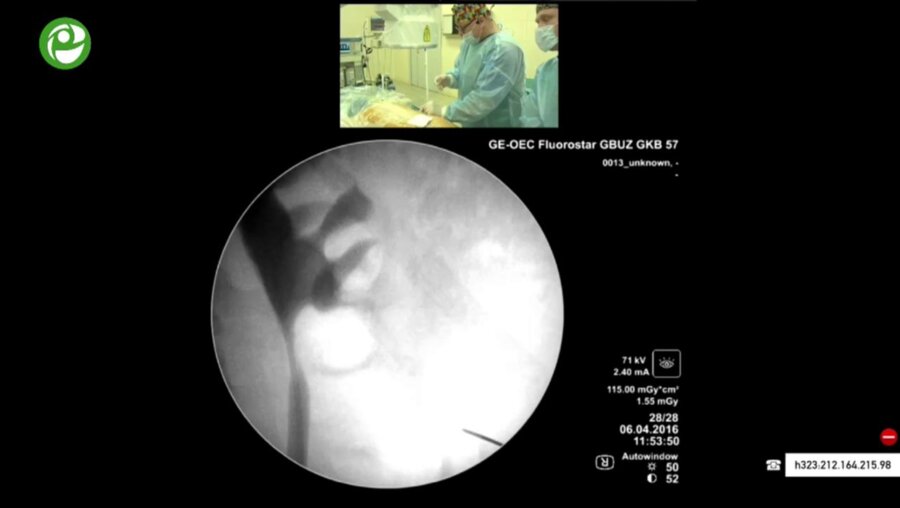

Мастер-класс по перкутанному лечению камней почки

06 апр 2016

3096 просмотров